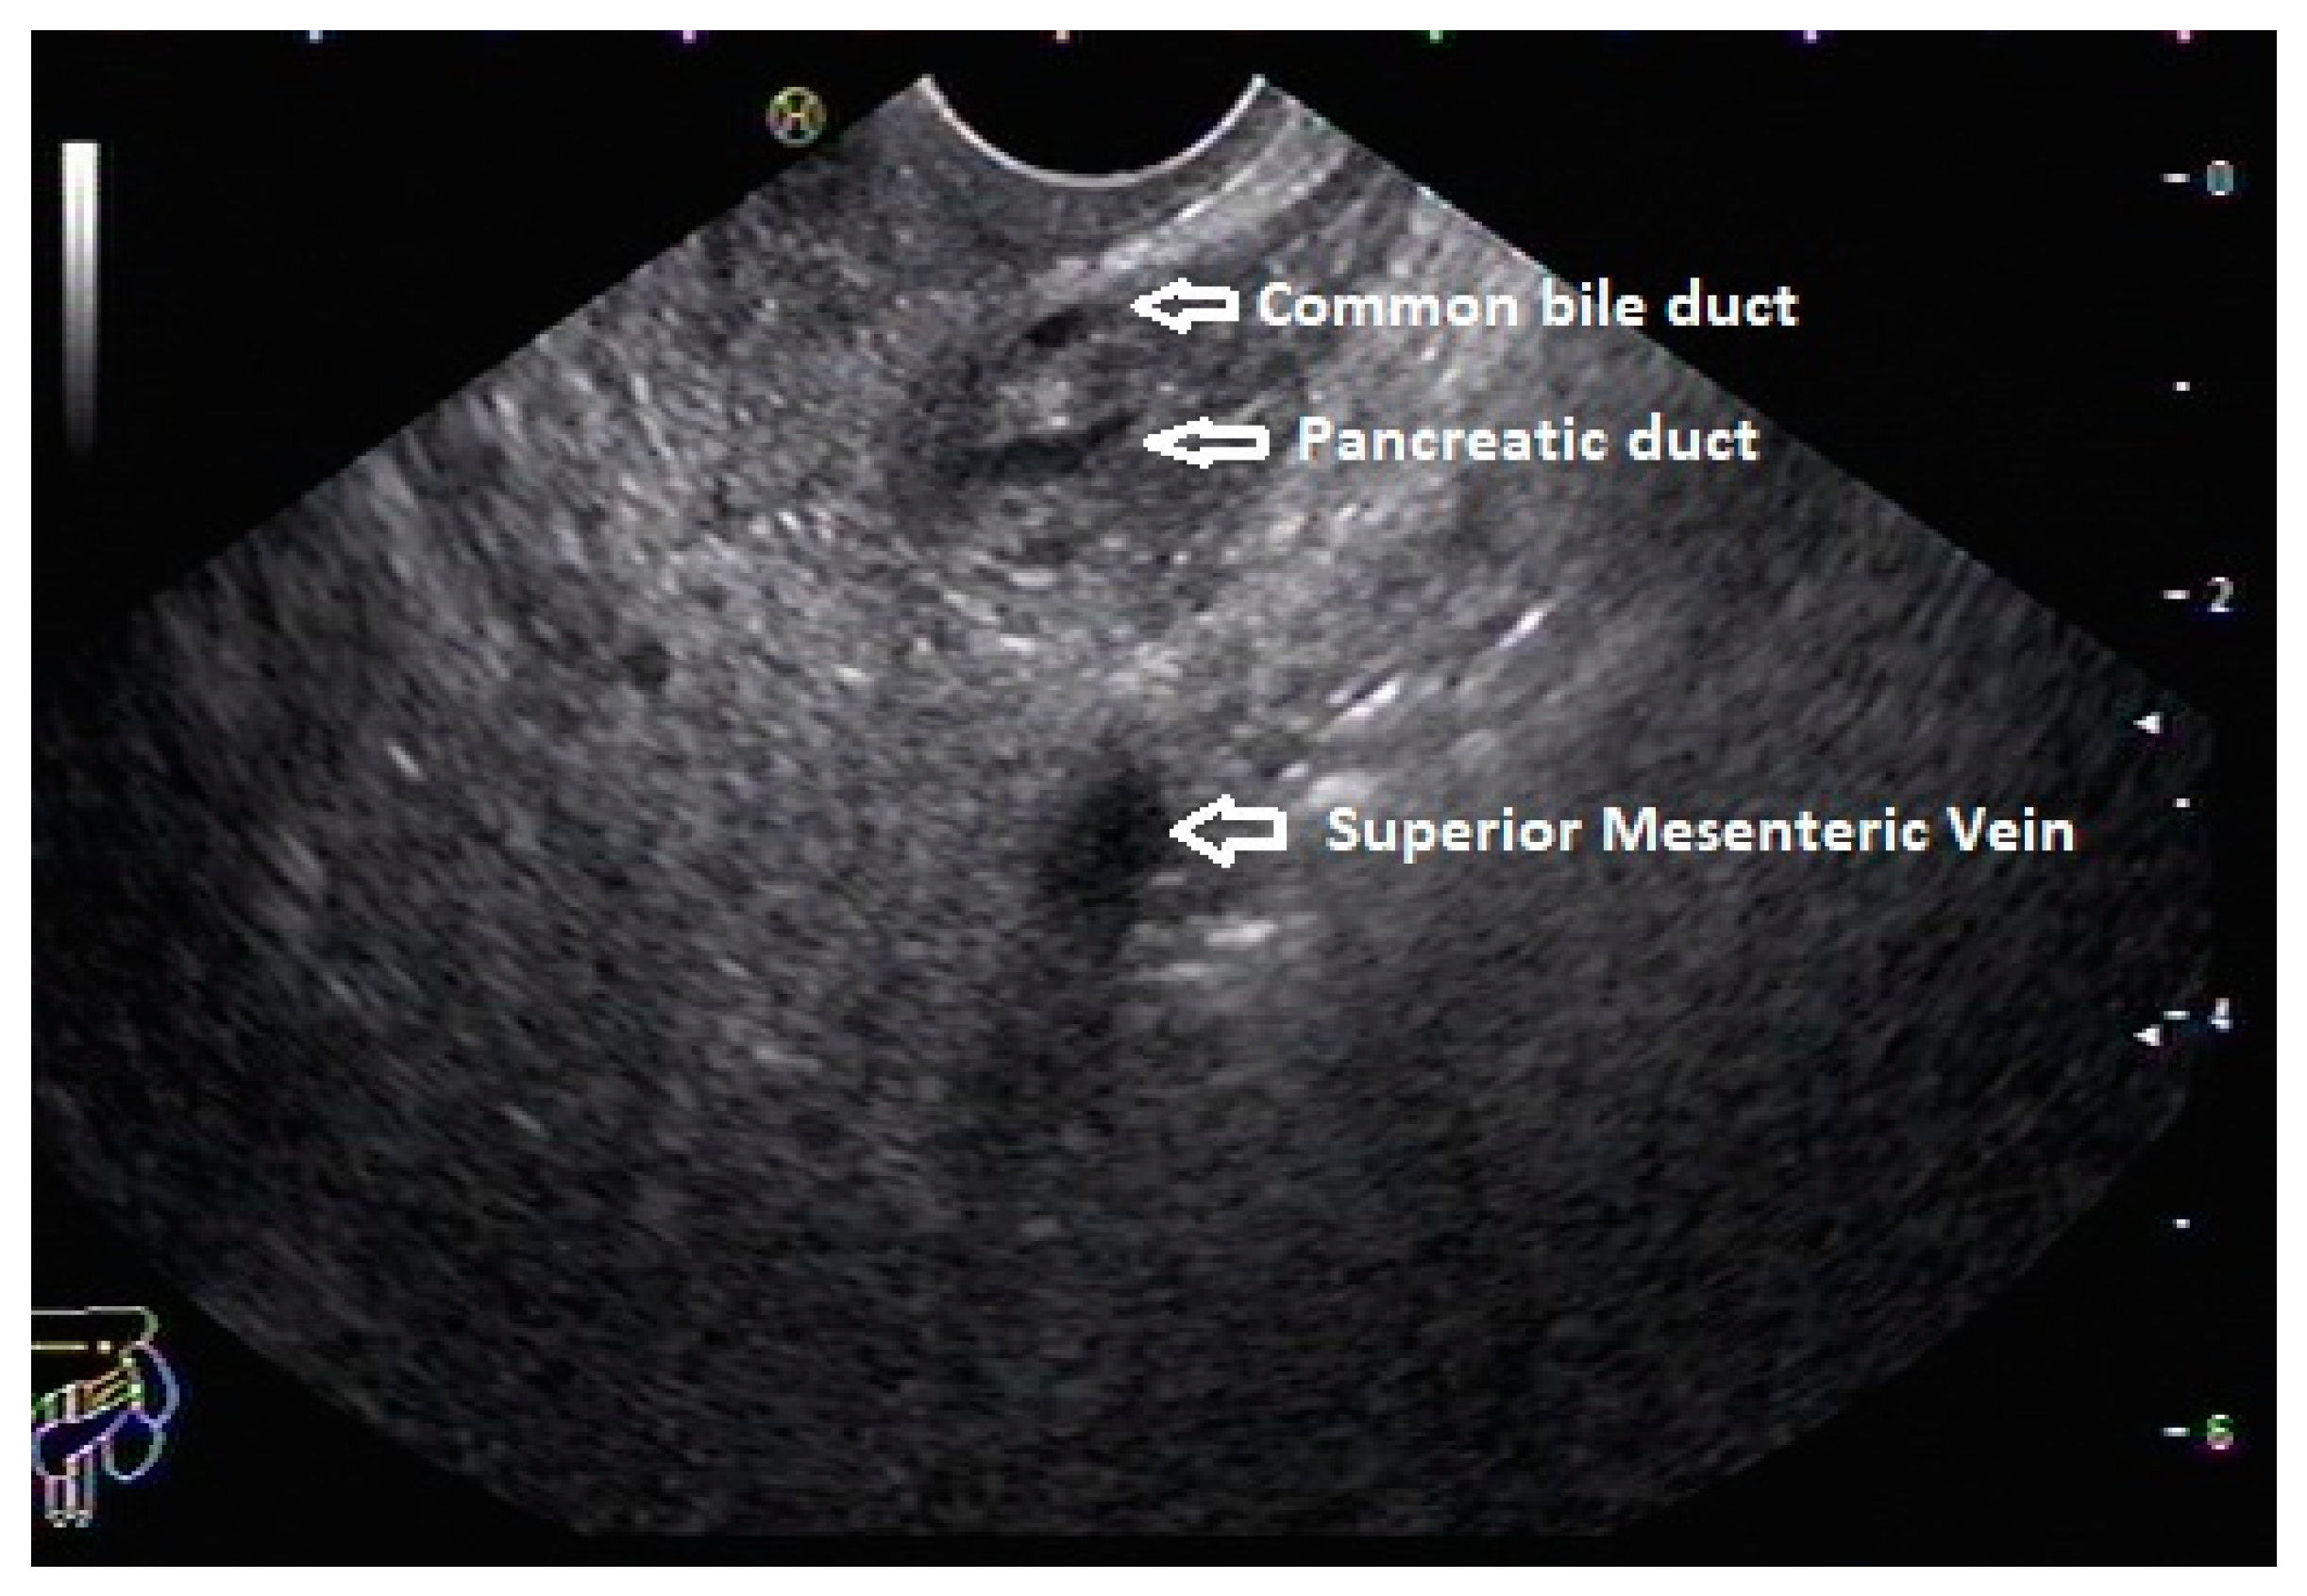

5. Pancreas Divisum

6. Endoscopic Ultrasound Features of Pancreas Divisum: Radial and Linear EUS